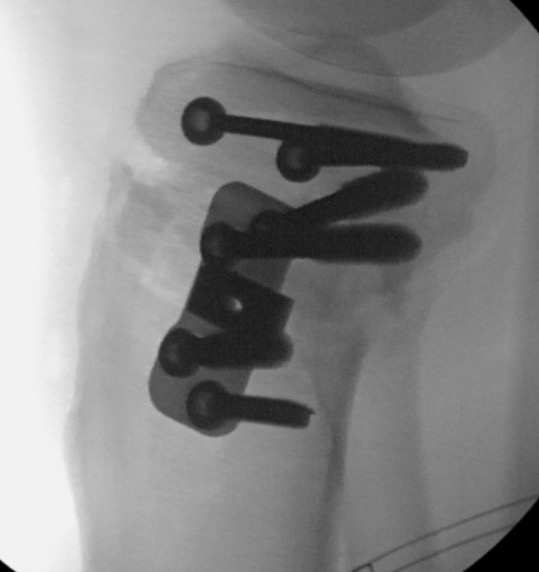

Management

Type I: limit weight bearing 6 weeks

Type II / displacement: lateral plate

Instability

- place a Richards staple / plate over lateral fracture site